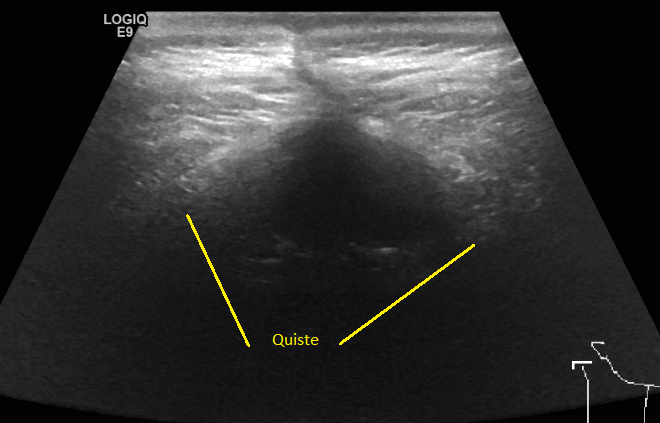

En noviembre 2019 6.8 x 3.5 x 1.6 cm y 20 centímetros cúbicos.

En enero del 2020 5.5 x 2.4 x 1 cm y 7.6 centímetros cúbicos

27 Julio 2020 4.1 x 3.0 x 1.6 cm y 11.04 centímetros cúbicos y un trayecto fistuloso de 0.7 cm.

Siguiendo la curva de disminución el quiste debió ser mínimo, pero aumento 4 centímetros cúbicos, no quiso ni abrir el sobre con los resultados, porque ya los había visto, se limito a decirme "Eso no puede ser posible, si fuera cierto no te sentirías ni te verías bien", "Seguramente quién lo realizó no lo comparó con los estudios previos o no supieron cómo hacerlo" "Doctor me lo hice aquí, no creo que se hayan equivocado" "¡Pues no!, yo no puedo tomar como válido este estudio así que necesito que te hagas una resonancia de cráneo"

El 6 de agosto regresé con los resultados de la resonancia, análisis de sangre y orina, esta vez yo tuve los resultados primero, así que al verlo lo primero que dije fue "¿Qué pasa doctor que mi cuerpo sigue rechazando el parche?", la resonancia confirmó lo mismo el quiste media 4.2 x 1.7 x 2.9 cm y 10 centímetros cúbicos y la fistula 4.8 mm y el remanente del tumor es de 15.1 mm, en contraste con en el ultrasonido 4.1 x 3.0 x 1.6 cm y 11.04 centímetros cúbicos y la fistula 0.7 cm.